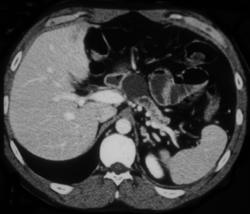

Islet Cell Cancer of the Pancreas